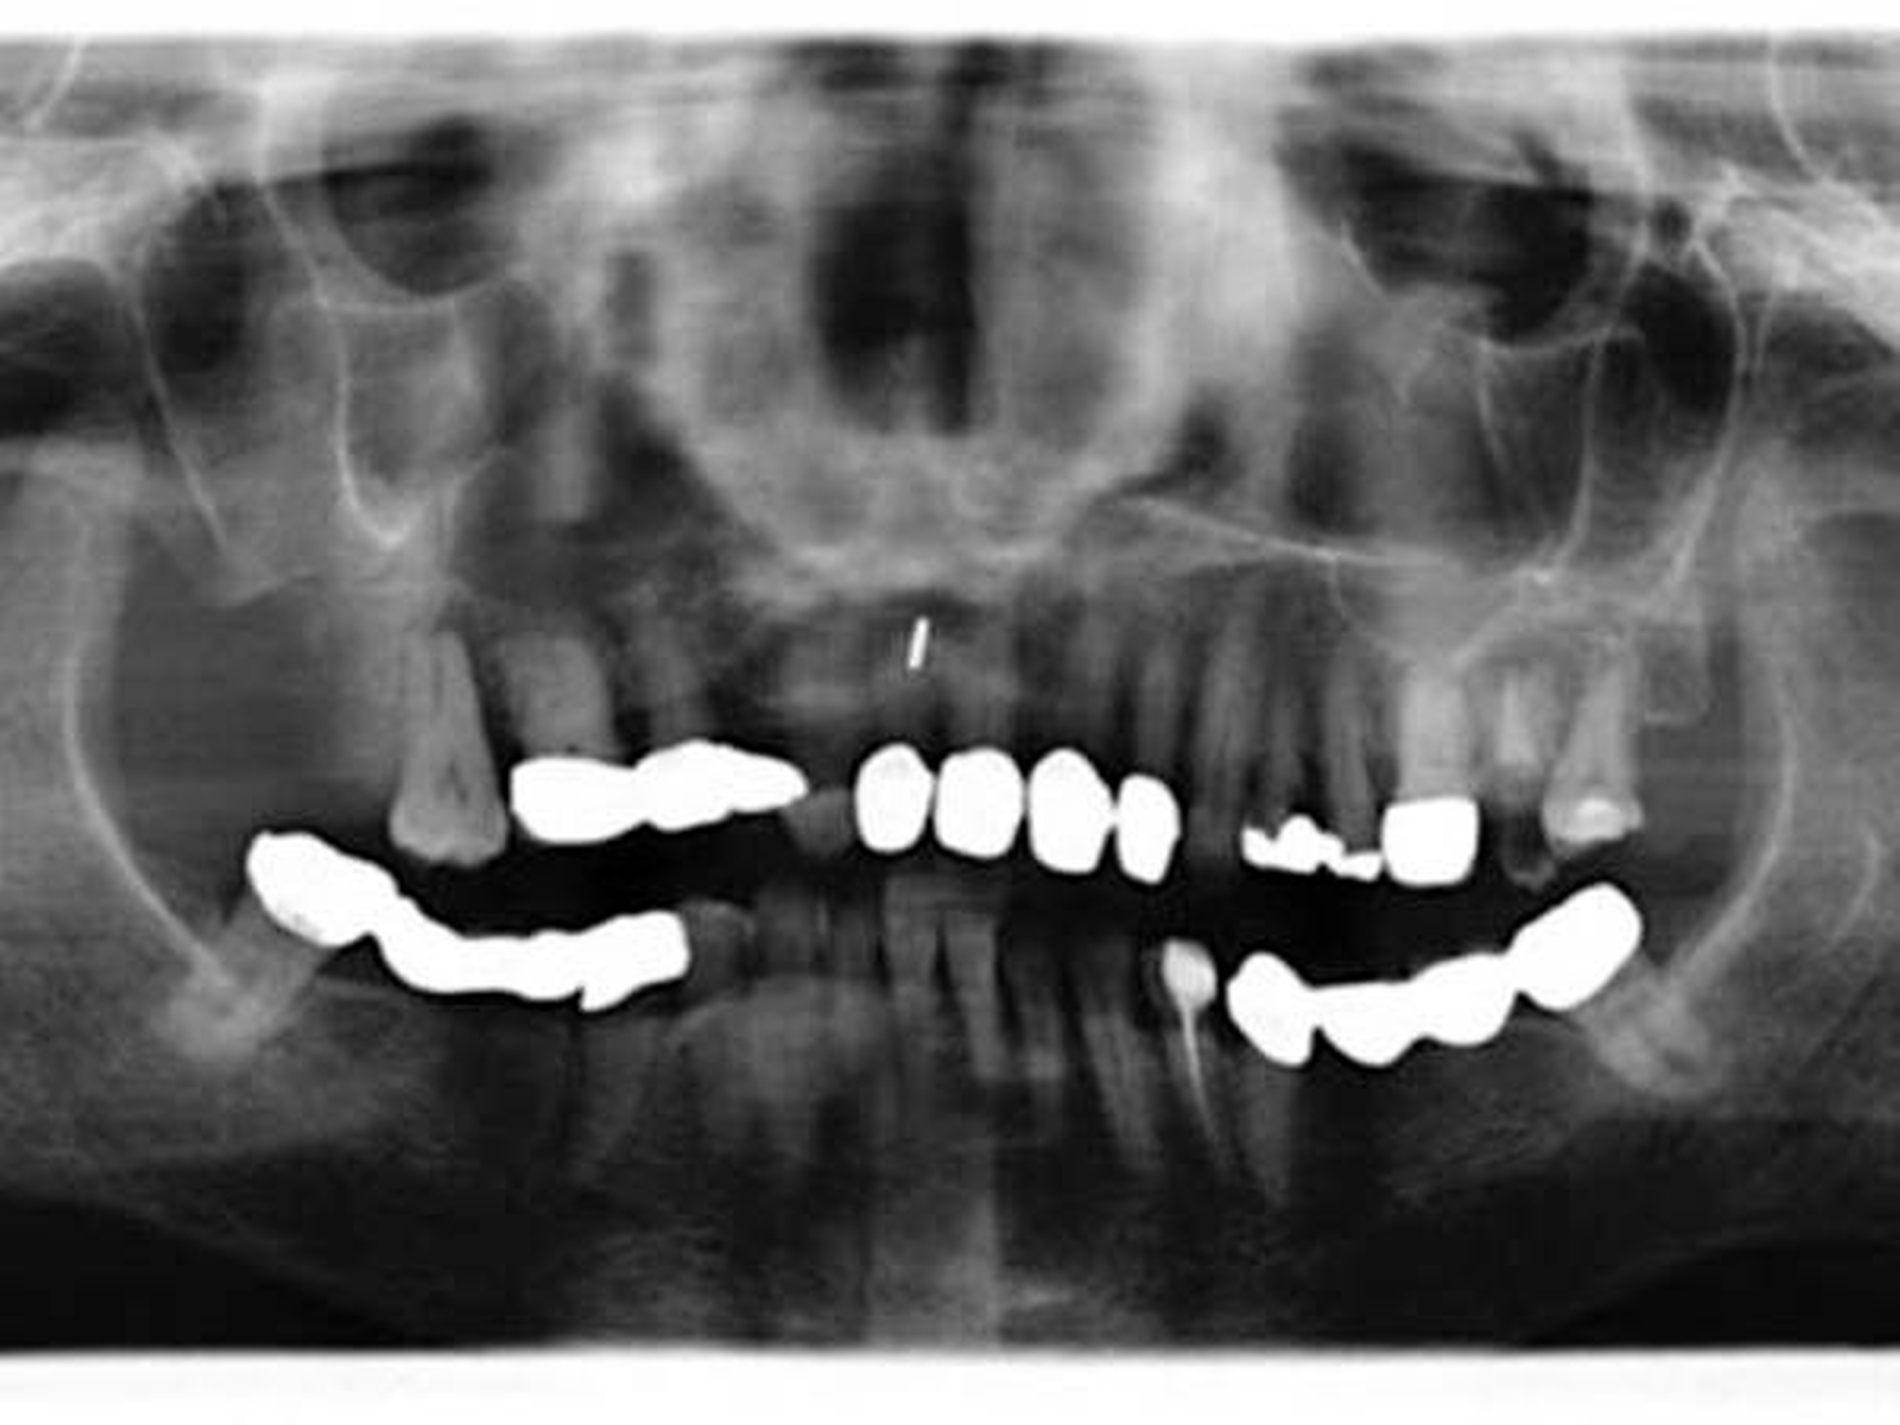

Nach Anlage eines temporären Tracheostomas und Neck Dissection Level I-III rechts erfolgte die Tumorexzision von transoral via midfacial degloving. So konnte auf eine extraorale Erweiterung des Zugangswegs nach Weber-Dieffenbach verzichtet werden.

Insgesamt wurden die Zähne 15 bis 17 und 26 bis 28 mit entfernt, und die Defektausdehnung umfasste somit eine distale Zweidrittel-Maxillektomie, also rechts ab Zahn 14 und links ab Zahn 26 nach distal mit Resektion bis in die Fossa pterygopalatina.

Bei Ausgang des Tumors von den kleinen Speicheldrüsen im Bereich des harten Gaumens und in Zusammenschau mit den üblichen Staging-Untersuchungen ergibt sich folgende postoperative Tumorklassifikation [TNM 8. Auflage 2017]: pT3, pN1(1/6), M0, L0, V0, Stadium III, Differenzierungsgrad G1, R1.